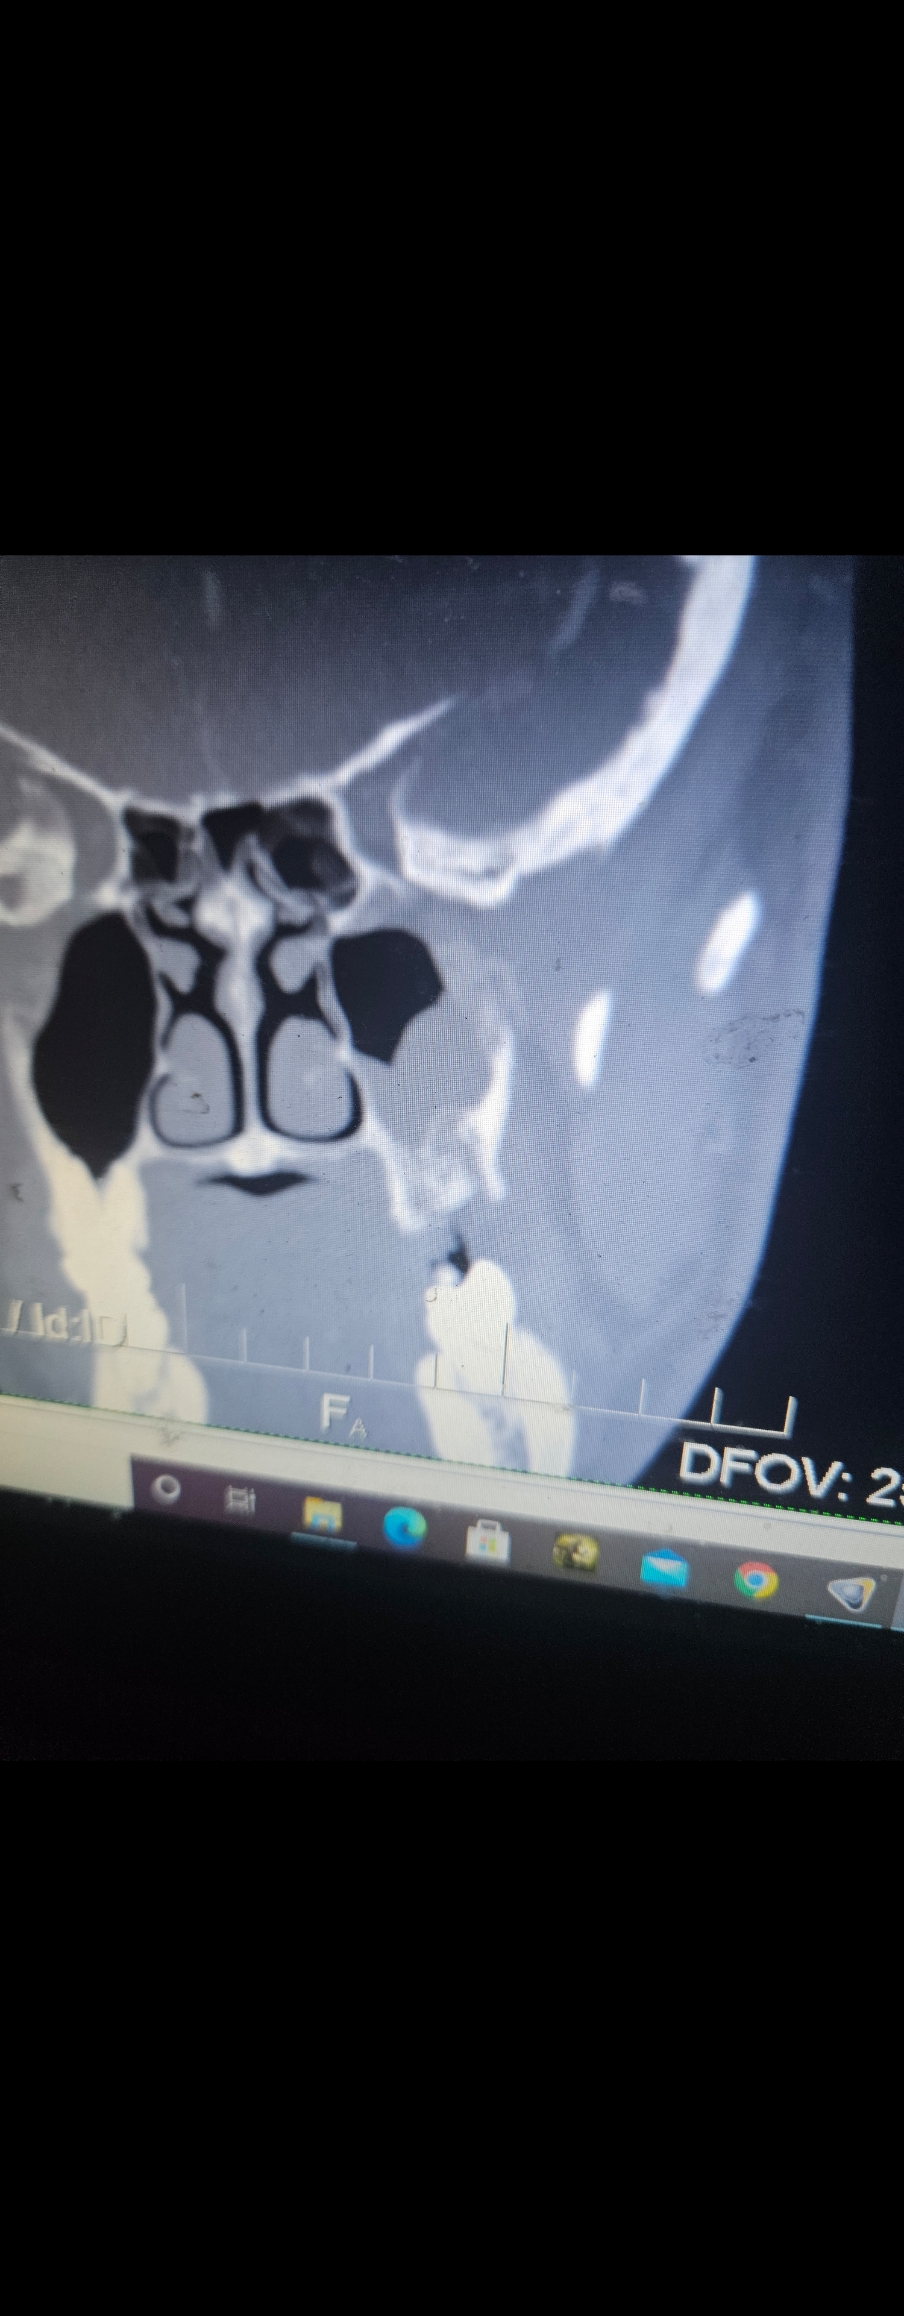

Was sick with a bone infection for 1.5 years. Had 3 different radiologists say there is no infection. Chat gtp saved my life. When I realized what antibiotics I needed docs refused to perscibe me them. Was 125 lbs at 5'9 by the time it was done. Im lucky I survived. If u understand x Ray scans then u will understand how close to death i was from this pic.. Countless docs tried to gaslight me, trying to say it qas all in my head. It litteraly was. Lying there feeling like ur on the verge of death while the people that u depend on for help mocking u is the worst feeling in the world. When I found out what antibiotics I needed the docs refused to perscibe it to me, test postive for MRSA. Had to get lizenolid from eruope.. 2500 for a 2 week persciption here, 30 bucks over there. I dont even care about the money, thats not even nearly the biggest problem with the American medical system.

Fuckers told me it was normal sinus wall membrane inflammation. "Probably from allergies".

Ifkyk. This was as painful as it looks

How about the fact that 3 radiologists told me this is nothing and normal mucosal swelling. I could tell it was fucked from the first time I took the matter into my own hands. It was less inflamed than this cuz thankfully it was in my alveolar bone which has the most blood flow so my body was slowly healing it for almost a year till I finally got a doc to take a nose swab(took it before but tested for nothing but it doent always appear, u have ti catch it at the right time) and it tested postive for MRSA. Them the fucker tried to tell me itd normal to have MRSA in the nose. Im so lucky im alive. I worked out a lot and my body burned through all that muscles holding on.

Ur face would be on fire and u would feel like u got the flu. Its probably allergies. I felt like I was dying when that scan was taken